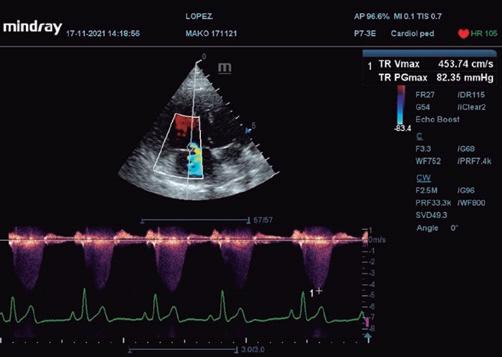

Figuras 2A y 2B. Imágenes de regurgitación mitral en ecocardiografía (corte paraesternal longitudinal derecho). Visualización de la válvula mitral con Doppler color (2A) y corte paraesternal apical izquierdo. Visualización de la válvula mitral con Doppler continuo (2B).

Según el consenso ACVIM de 2020 sobre diagnóstico y tratamiento de la hipertensión pulmonar en perros5, el patrón vascular en radiografía pulmonar puede acercarnos al diagnóstico de hipertensión pulmonar. Sin embargo, es necesaria la confirmación mediante ecocardiografía, considerando signos de hipertensión pulmonar una regurgitación tricúspide mayor de 3 m/s (normal menor de 2,8 m/s) y/o aplanamiento del septo IV. Por lo tanto, trataremos con venodilatadores como el sildenafilo (2 mg/kg/12 h) cuando: • Haya presencia de síntomas (episodios sincopales o presincopales). • Haya signos de sobrecarga de presión o volumen derecha en el estudio ecocardiográfico: aplanamiento de septo IV, acompañado de velocidades de regurgitación tricúspide aumentada (figura 6).